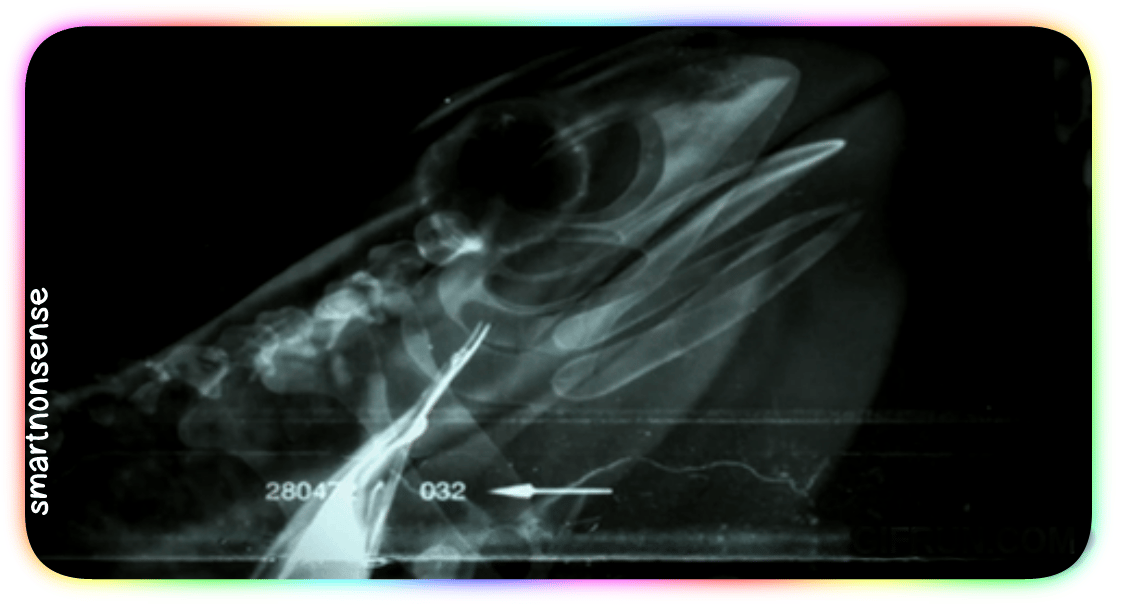

Check out this X-ray:

When you go to swallow that fly, your eyeballs (which – you know – usually just sit in their sockets)

Get PULLED down by muscles

Into your skull!

They press HARD on the roof of your mouth:

Driving that meal straight down your throat!